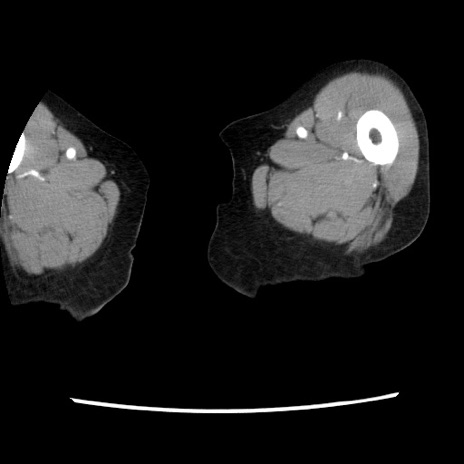

症例1(横断像)

症例

【症例】80歳代女性

【主訴】腹痛

【現病歴】8時間前から腹痛あり来院。

【既往歴】糖尿病、脂質異常症、子宮体癌にて子宮全摘術

【身体所見】意識清明・会話良好だが腹痛で苦悶様、全腹部にわたって反跳痛と圧痛あり

【データ】WBC 13600、CRP 0.14、LDH 224、CK 90